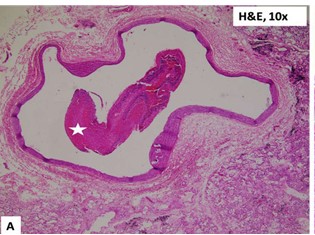

Histologic section of a hilar pulmonary vessel showing an occlusive blood clot (white star)

Description: No description available.